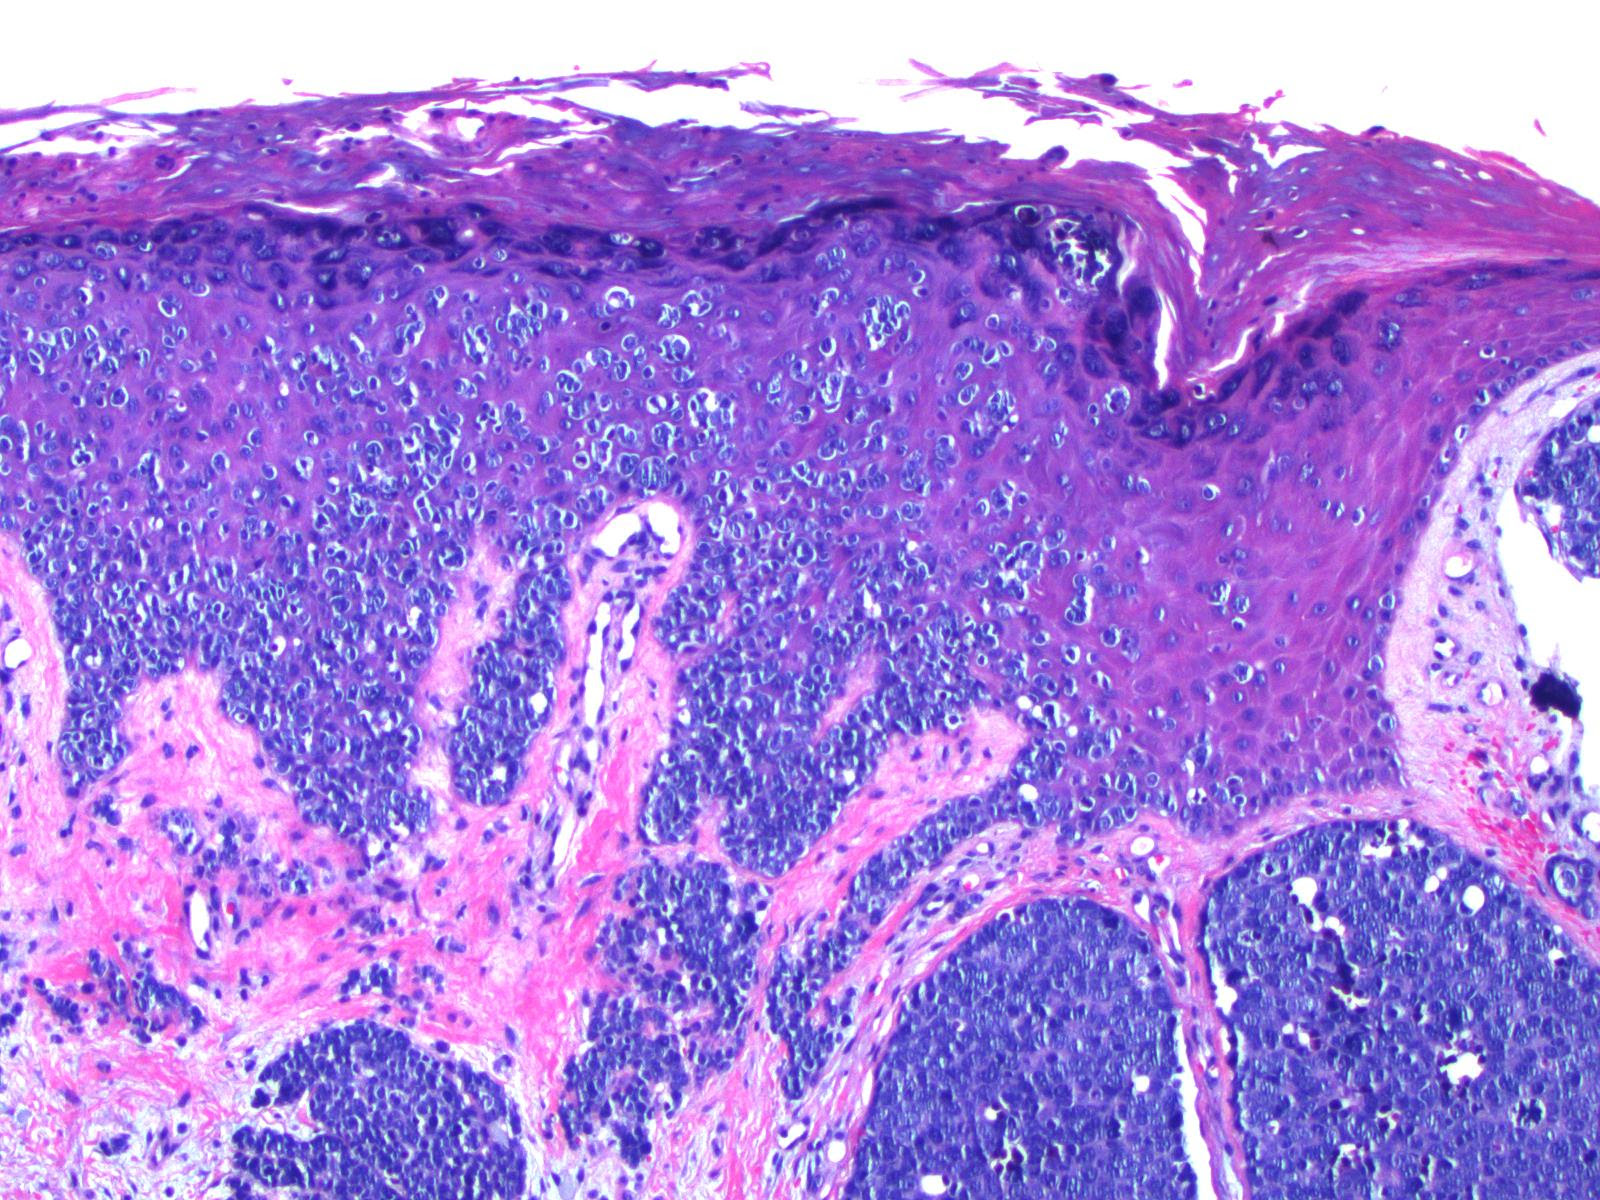

cancer wikipedia. Patients with melanoma in situ (level zero) have cancer cells best inside the outer layer of skin (epidermis). There may be no invasion of the deeper layer (epidermis) and therefore basically no potential for spread. Melanoma in situ is curable by using ok elimination with surgical procedure. In situ melanoma research basis. What is cancer? Most cancers remedy centers of the usa ctca. Degree 0 melanoma (in situ) aim at melanoma. In degree 0 cancer, the malignant tumor remains confined to the top layers of the skin (dermis). Which means the most cancers cells are simplest inside the outer layer of the pores and skin and have now not grown any deeper. The time period for that is in situ, this means that “in region” in latin. Melanoma remedy pdq countrywide most cancers institute. Level zero (melanoma in situ) treatment of level zero is commonly surgical operation to remove the region of extraordinary cells and a small quantity of everyday tissue around it. Use our clinical trial search to locate ncisupported most cancers scientific trials which might be accepting patients. Melanoma in situ (stage zero) cancerconnect news. Sufferers with cancer in situ (degree 0) have melanoma cells best within the outer layer of pores and skin (dermis). There's no invasion of the deeper layer (epidermis) and consequently.

melanoma at its most curable skincancer. To diagnose cancer in situ (or any melanoma), a medical doctor performs a biopsy on the suspicious spot, removing tissue and sending it to a lab to be interpreted with the aid of a certified dermatopathologist. Jim’s prognosis of melanoma in situ. Cancer in situ (degree zero) cancer most cancers research united kingdom. Cancer in situ is likewise referred to as degree 0 cancer. It approach there are cancer cells in the pinnacle layer of skin (the epidermis). The melanoma cells are all contained inside the region in. Cancer treatment pdq national cancer institute. Answer questions, resolve issues, locate thought. Search our associated articles now! Over 85 million visitors. Cancer in situ (level zero) cancerconnect news. The cancer studies basis (mrf) is main the melanoma network to convert melanoma from one of the deadliest cancers to one of the maximum treatable thru research, training and advocacy. The cancer studies foundation is a 501(c)(three) nonprofit enterprise. Malignant melanoma in situ stage 0 pores and skin most cancers. Malignant melanoma in situ impacts the dermis of the skin; sufferers with this stage of skin most cancers can normally be handled without a headaches. Analyze greater. Answer questions, resolve problems, find idea. Malignant melanoma in situ affects the epidermis of the pores and skin; sufferers with this level of skin cancer can commonly be handled with out a headaches. Study more.

In situ cancer studies foundation. The melanoma studies basis (mrf) is main the melanoma network to convert melanoma from one of the deadliest cancers to one of the most treatable thru studies, schooling and advocacy. The cancer research foundation is a 501(c)(3) nonprofit organisation. Melanoma in situ (stage zero) cancer cancer research united kingdom. Cancer in situ is also referred to as degree 0 melanoma. It approach there are cancer cells in the pinnacle layer of pores and skin (the dermis). The melanoma cells are all contained in the region in. Degree 0 melanoma (in situ) aim at cancer. In degree 0 melanoma, the malignant tumor is still restrained to the higher layers of the skin (dermis). Which means that the most cancers cells are best inside the outer layer of the skin and have not grown any deeper. The time period for that is in situ, which means that “in area” in latin. Melanoma in situ melanoma in situ about. Cancercenter has been visited by means of 10k+ users inside the past month. Malignant melanoma in situ stage zero pores and skin cancer. Cancer in situ is likewise known as degree zero melanoma. It means there are most cancers cells within the pinnacle layer of pores and skin (the epidermis). The melanoma cells are all contained inside the place wherein they began to develop and have no longer grown into deeper layers of the skin. Some doctors call in situ cancers pre most cancers.